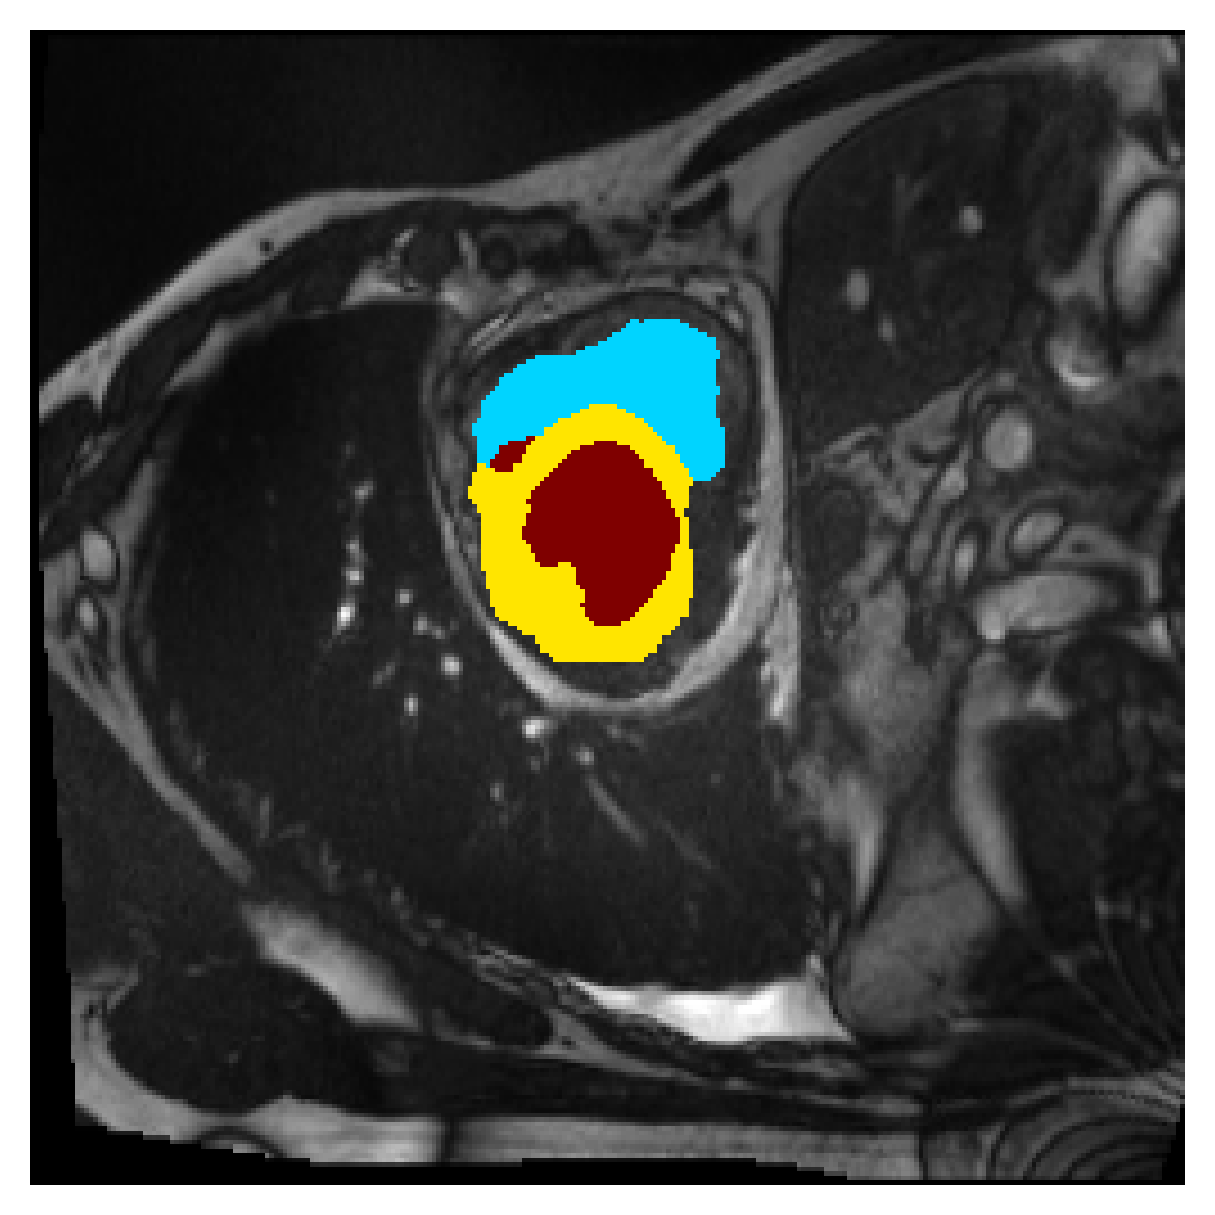

5.1 Segmentation of cardiac structures

The average 3D Dice scores and HD95 values on the ACDC test set are given in Table 2, and boxplots in figures 4 and 5 show the distributions. We see that, in terms of DSC, the proposed strategy of using intensity-aware distances withing boundary loss performs better than simply using the Euclidean distance, with the best results achieved by using the strictly intensity based MBD. The HD95 however favors the original version of , which may be do to its smoother predictions and less fragmentation and oversegmentation. The CRF-loss results are significantly worse in both metrics.

In Figure 3 we show the 3D DSC validation curve evolution for a single run. The CRF-loss seems to have converged to a low DSC value, while all settings combining CE and boundary loss reach values close to the full supervision in the beginning of the training and then slowly collapse towards to the point annotations. The MBD version stands out, degrading slower, thus providing a wider range of potentially good models for evaluation.

Qualitative comparison

In Figure 6 we provide qualitative results on a number of randomly chosen test set slices. Upon visual inspection, we can observe that training with the intensity-aware distances (particularly with and ) follows the image gradients better and is better at recovering the underlying shape than the Euclidean version. The CRF-loss seems to recover the shape of the myocardium and left ventricle to some extent, but fails entirely on the right ventricle.